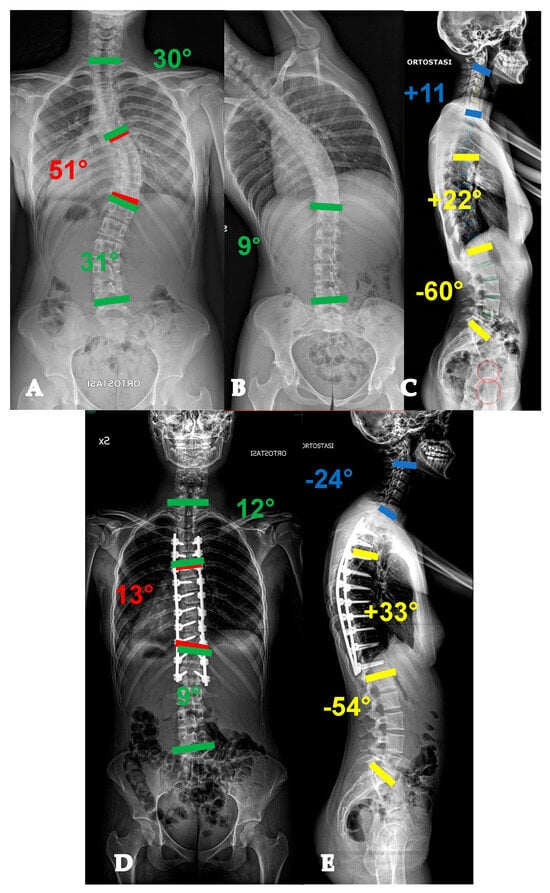

- For curves ≥ 90° AND with a flexibility index < 15% (YADIS 2B), the HiPoAD technique, even though it proved to be effective for this kind of curve when addressed during adolescent years [12], may not be powerful enough for YAdIS 2 patients. These cases should be addressed with a three-columnar approach. One strategy could be to adopt three-column osteotomies like VCR. A possible alternative, in order to avoid the risks of a three-column osteotomy, is to perform a three-columnar release through a combined approach: an anterior thoracoscopic release (wide resection of anterior longitudinal ligament and multiple periapical discectomies), followed by a posterior column release based on multiple Ponte Osteotomies and a posterior correction (VT-HiPoAD, Videothoracoscopic release—HiPoAD) (Figure 4).